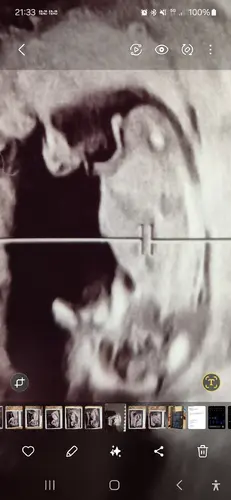

In the 3rd picture it looks

Like a boy. The other 2 girls